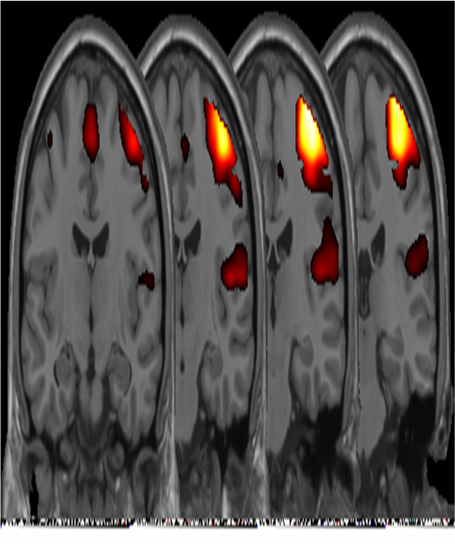

Activation of motor cortex - left finger tapping The change in MRI signal with oxygenated hemoglobin fraction is very small and is complicated by a delayed response to the neural activity called the hemodynamic response. These things make it difficult to detect the pattern even in areas that are active. We do as much as we can, but in the end, the identification of active areas is a statistical decision and there is nothing certain.